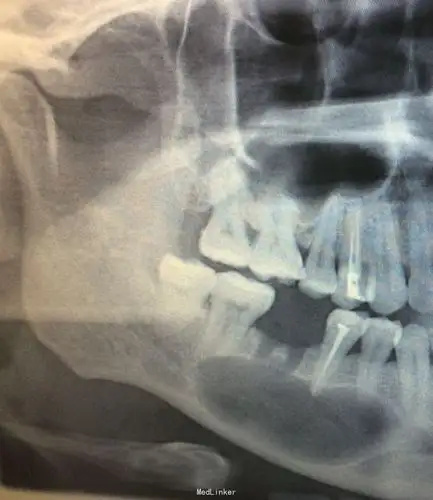

多发性颌骨囊肿综合征一例

典型的下颌骨含齿囊肿

右下颌骨角化囊性瘤

开窗减压术治疗颌骨囊肿一例

左上前牙牙源性颌骨囊肿一例